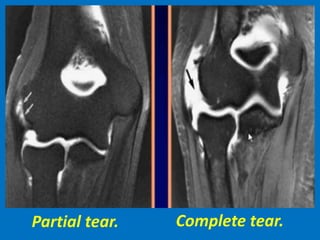

Ulnar collateral ligament (UCL) injury refers

to a sprain, partial tear or complete tear of

the ligament that traverses the inside (or

medial side) of the elbow. The UCL is the

primary stabilizer of the elbow and plays an

important role in throwing and hitting

sports, such as baseball, football and tennis.

Additional findings: Strain or rupture of the

common flexor tendon, ulnar neuropathy,

ulnar traction spurring or heterotopic

ossification of the soft tissues

and medial flexor insertion pronator tear.

Partial tear. Complete tear.